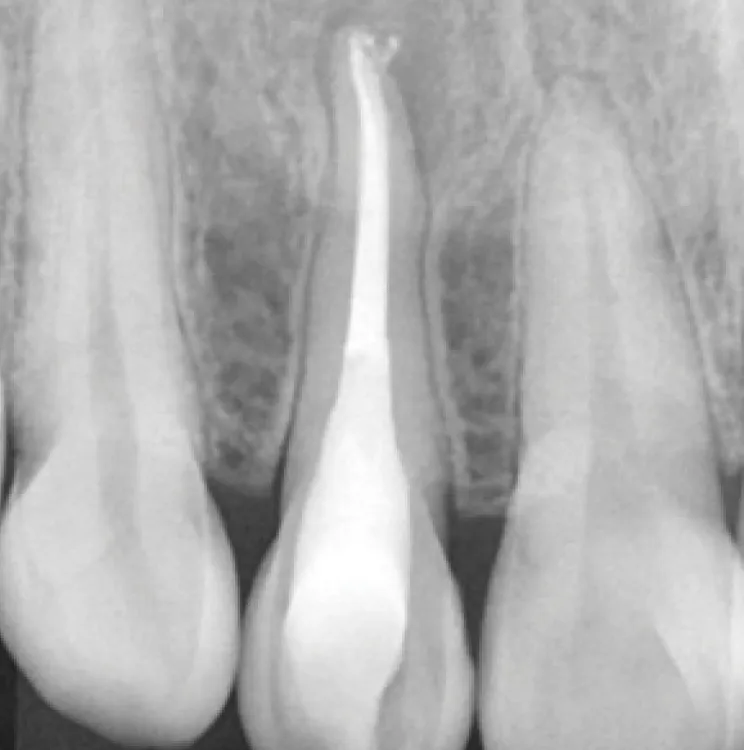

Cas clinique

Résultats clinique

1

Avant le traitement

2

Après le traitement

3

15 mois plus tard